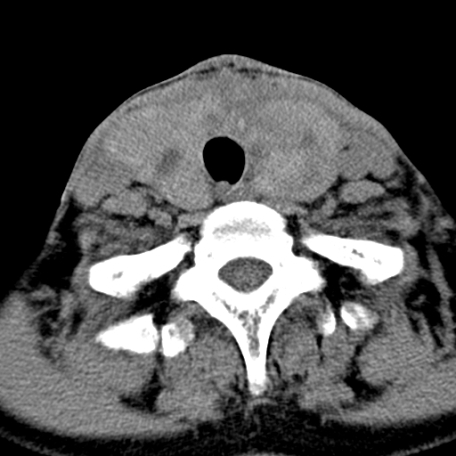

标题: CT24010:患者女56岁双侧甲状腺摘除术后一月复查,患者现感 [打印本页]

标题: CT24010:患者女56岁双侧甲状腺摘除术后一月复查,患者现感

甲状腺术后复发,现在甲状腺区域仍有密度不均匀之软组织密度影。

甲状腺区域密度不均匀密度影,应该是术后改变,要鉴别是否复发,建议增强检查。

“甲状腺摘除术后一月复查”,有病理吗?考虑术后复发,可能是恶性,颌下及左侧颈部淋巴结有肿大。

考虑术后复发,并颈部淋巴结肿大。请结合临床。

双侧甲状腺肿大,周围结构不清,术后复发时间有点短,考虑出血并感染。